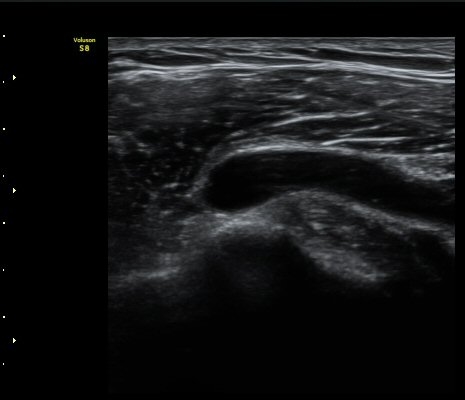

ÃÊÀ½ÆÄ °Ë»ç

2049205267_ba00cba1_IMG_20140331_2_3-c.jpg